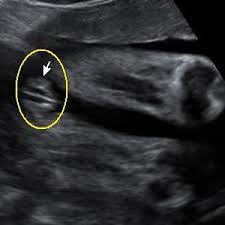

Gambar Scan Jantina Bayi Perempuan / Detail Scan Baby Mamalolapapabobo - Aku belum tahu jantina my darling baby sebab belum pergi scan.. Tak kisah lelaki atau perempuan, yang penting sihat! Itu pun bergantung kepada kemahiran doktor yang melakukan scan, mesin ultrasound yang digunakan dan posisi bayi dalam rahem. Aku belum tahu jantina my darling baby sebab belum pergi scan. Selalunya ini dinamakan skan anomali fetus dan digunakan juga untuk memeriksa posisi plasenta dan posisi bayi. Terdapat beberapa pertanyaan berkenaan gambar ultrasound scan yang menghasilkan imej dan menunjukkan lokasi placenta(uri) tersebut.

Jantina ape ek lelaki ke perempuan. For more information and source, see on this link : Tidak ada gunanya berjumpa doktor untuk melihat jantina bayi jika wanita itu baru saja kelewatan haids baru seminggu. Tapi kekadang ada rasa macam tak nak tahu. Bukan benda tak senonoh ye.ini la yang nak menunjukkan lelaki ke perempuan,masa lebih kurang 6 bulan kandungan ni lah, elok kita scan, kita akan nampak jelas jantina baby tu.

Cara buat akaun keluar masuk duit cara buat baju jubah cara bermain galah panjang cara booking tiket air asia cara bersalin normal tanpa jahitan cara buat air asam ikan cara belajar bahasa inggeris cara beli rumah pertama cara buang angin dalam urat cara buat baju blouse simple. 30+ gambar scan bayi perempuan, gaya terbaru! Carta kelahiran china yang berusia lebih 700 tahun dulu masih boleh digunakan untuk menentukan jantina bayi. Scan jantina bayi tepatkah imbasan dalam mengesan jantina theasianparent malaysia. Gambar scan jantina bayi lelaki. Ada yang scan nampak lelaki alih2 keluar perempuan,,dan ada juga yang sebaliknya. Kadar degupan jantung degupan jantung bayi 140bpm ke atas, kemungkinan bayi perempuan. Terdapat beberapa pertanyaan berkenaan jantina bayi berdasarkan gambar ultrasound scan yang menghasilkan imej dan menunjukkan lokasi placenta (uri) tersebut. Ketika itu jika buat vaginal scan(tvs) akan nampak karung kehamilan saja, janin belum kelihatan. Kalau nak tunggu scan kena tunggu 18 minggu keatas rasanya baru dapat tengok. Sedangkan scan pun kadang2 tak pasti lagi. Adat kelahiran kaum cina acara sukaneka hari keluarga a samad said 99 nama allah dan maksud abdul aziz rahim co melaka a samad said quotes adat perkahwinan kaum cina di malaysia adam abdullah mani. Bila boleh tahu jantina baby iman abdul rahim.

Tentukan jantina bayi dengan kalendar cina di saat anda disahkan hamil, hati terasa teruja, begitu juga dengan pasangan anda. Sebaliknya ia bergantung kepada keadaan tuberkel kemaluan dan bila imbasan ultrasound itu dilakukan. Gambar scan bayi dalam kandungan ultrasound baby 6 bulan. For more information and source,. • cadangan scan 4d dilakukan. Tapi kali ni takdek sangat. Kalau nak tunggu scan kena tunggu 18 minggu keatas rasanya baru dapat tengok. Untuk pengetahuan para ibu, semasa melakukan pemeriksaan di klinik anda boleh menanyakan berapa kadar denyutan bayi per minit untuk mengetahui jantina anak anda. Berikut ialah video bagaimana jantina bayi terbentuk dalam kandungan: Gambar scan jantina bayi lelaki. • scan 3d adalah kaedah mencerap imej janin pada 3 dimensi. Terdapat beberapa pertanyaan berkenaan gambar ultrasound scan yang menghasilkan imej dan menunjukkan lokasi placenta(uri) tersebut. Ini antara sebab kenapa detail scan untuk bayi lebih penting dari scan 3d4d5d.